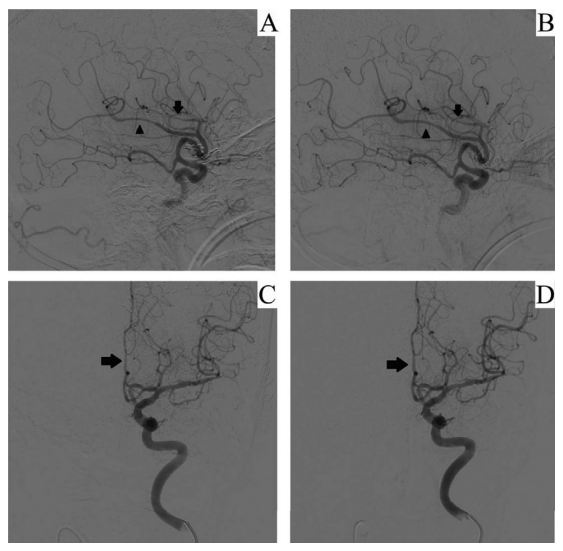

图2:病例1(A)动脉灌注尼莫地平前:胼周动脉(箭头)和胼缘动脉(箭头)血管痉挛。(B)动脉灌注尼莫地平后:双侧血管痉挛明显改善。病例2。(C)动脉灌注尼莫地平前;左侧大脑前动脉A2段(ACA)血管痉挛。(D) 动脉灌注尼莫地平后;A2节段直径明显改善。